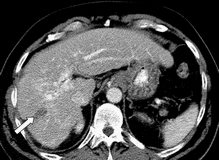

Hepatoselüler karsinomu (HCC), dünyada en sık görülen 6. malignite olup, her yıl yaklaşık 600 bin hastayı etkilemektedir. Ameliyat edilemeyen veya metastatik hastalığı olan kişilerin medyan sağkalımı yalnızca birkaç aydır. Kanıtlanmış bir sağkalım yararı olmamasına karşın, doksorubisin, HCC tedavisinde rutin olarak kullanılmaktadır. Sorafenibin de plaseboya kıyasla medyan sağkalımı istatistiksel olarak anlamlı düzeyde iyileştirdiği ortaya konmuştur. Yapılan faz I çalışmada, solid tümörlü hastalarda sorafenibin doksorubisin ile birlikte etkinliği ve tolere edilebilirliği değerlendirildi ve ümit verici sonuçlar elde edildi. Bununla birlikte, ilerlemiş HCC hastalarında sorafenib ve doksorubisin tedavisinin etkinliği faz II veya III çalışmalarda değerlendirilmedi.